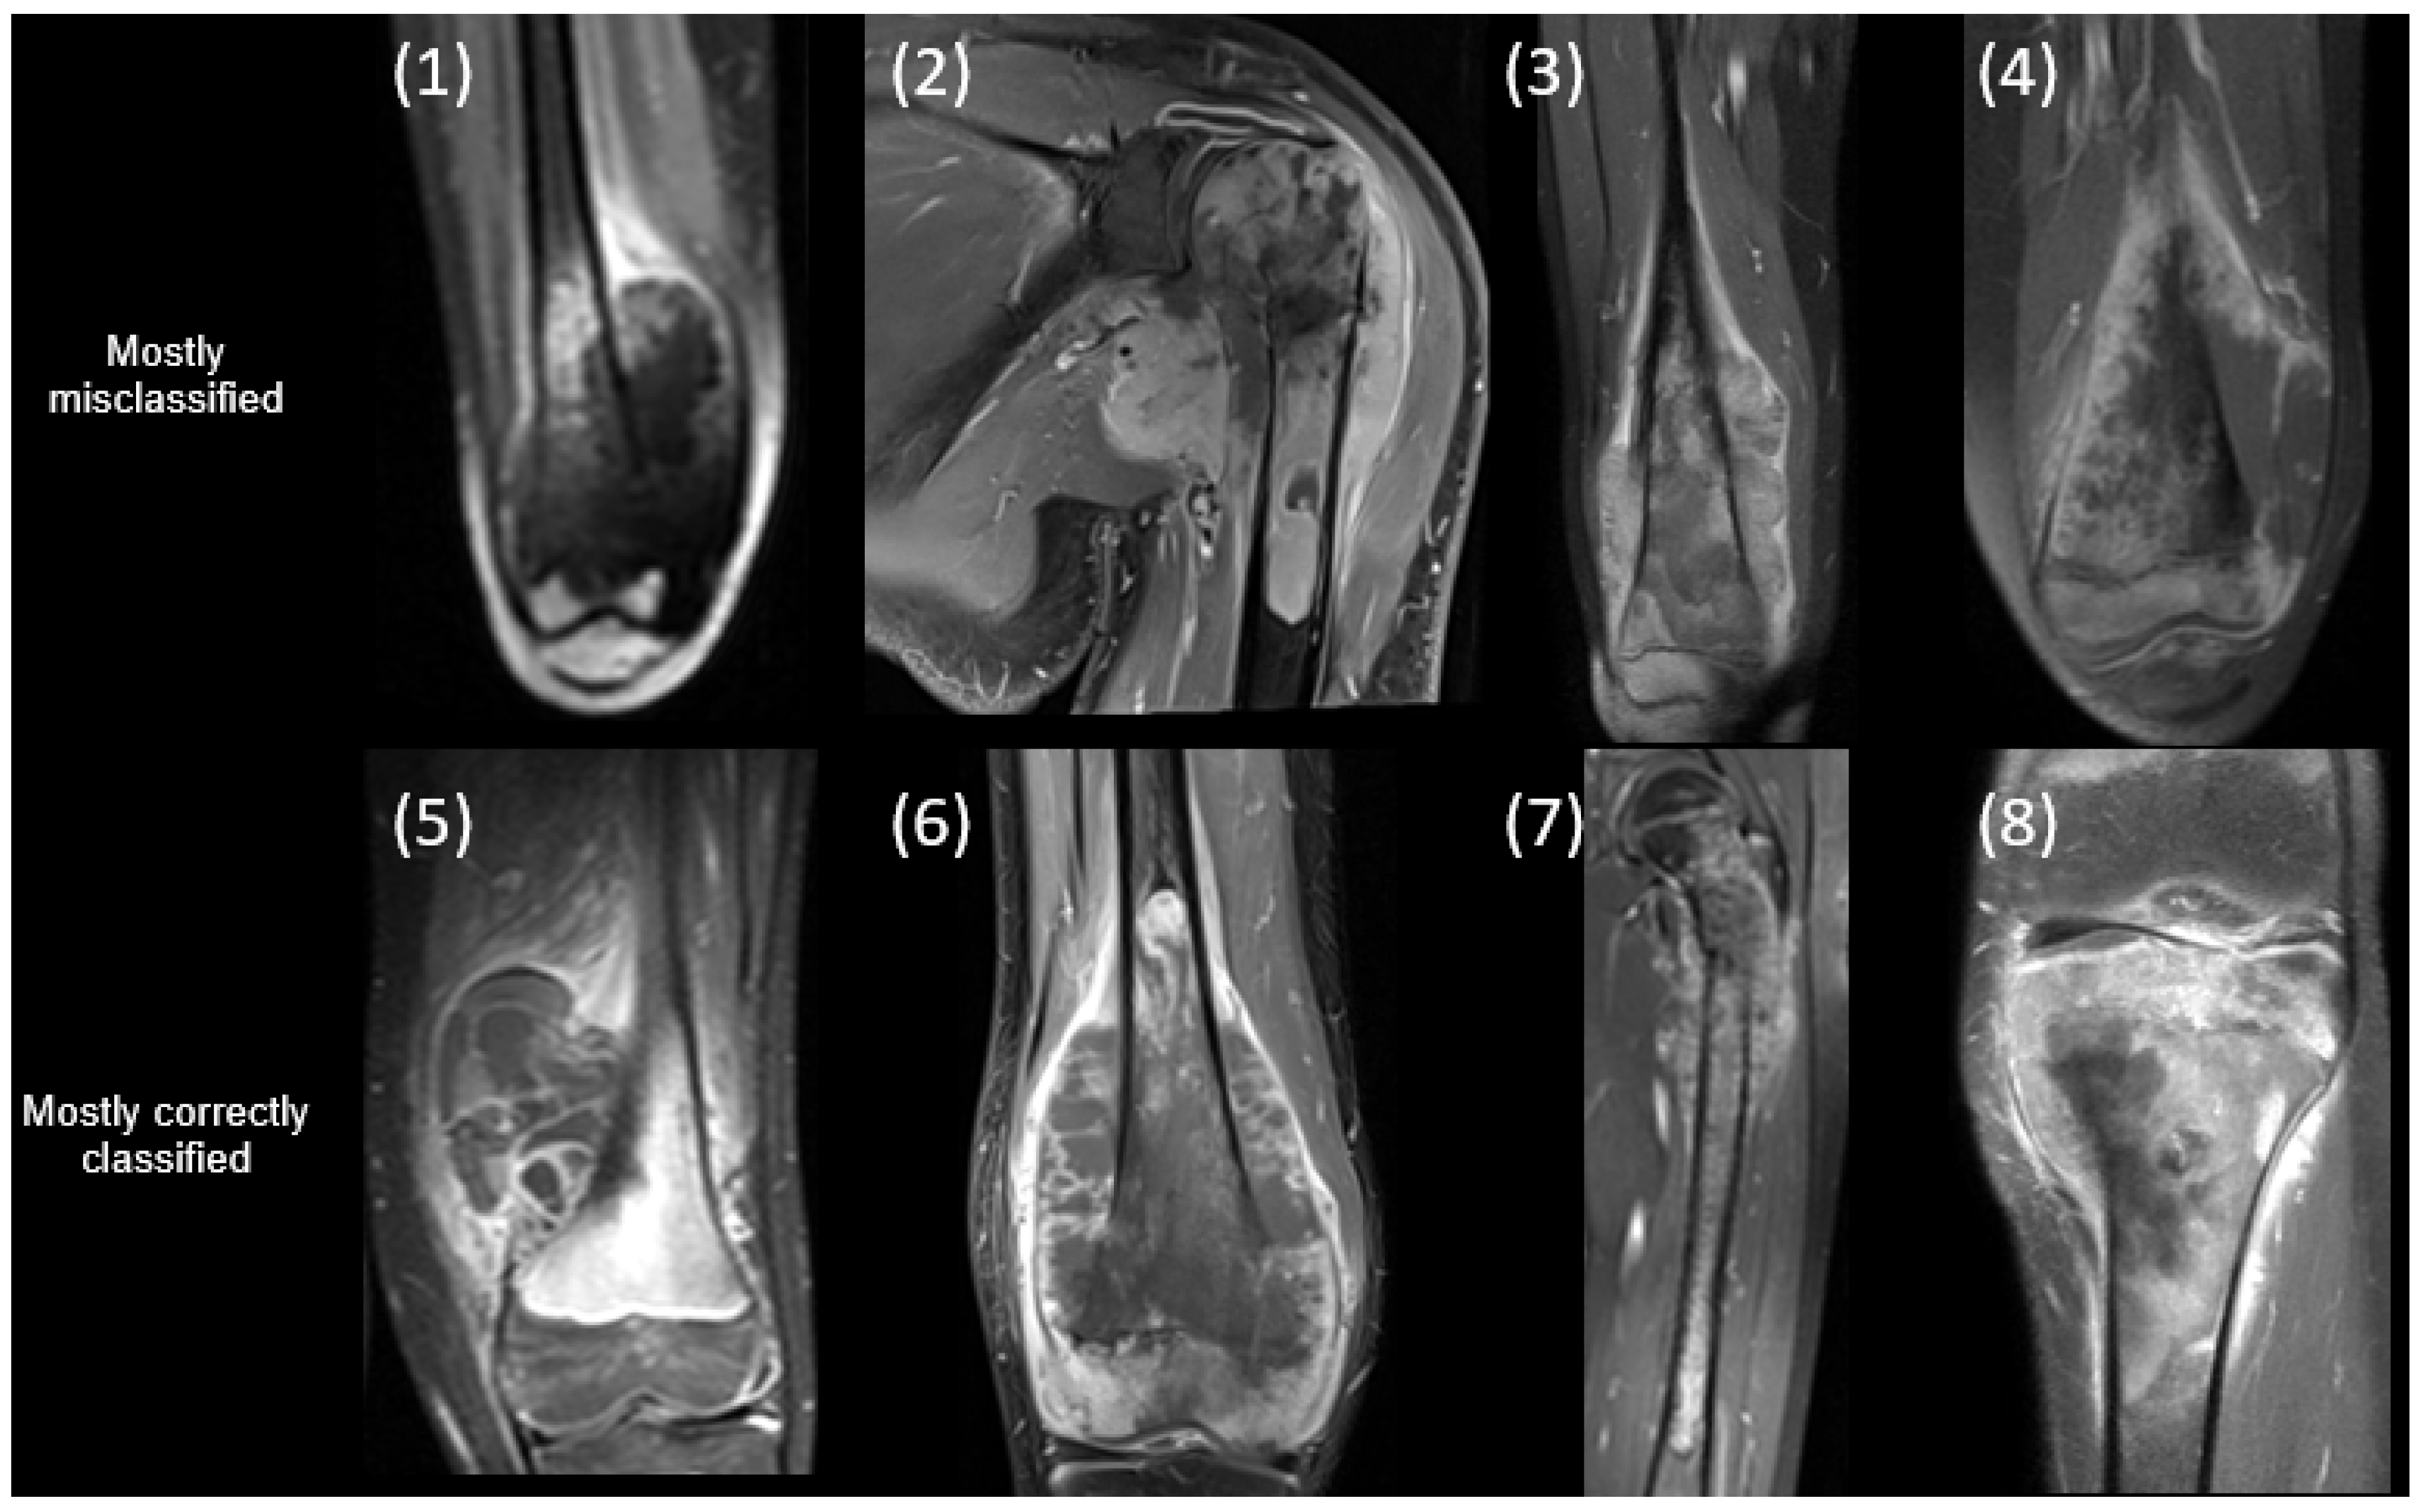

| Patient | Gender | Age (y) | Skip Lesion | Meta-Stasis | OS Type | Progressive Disease | % Necrosis | Relapse off Therapy | Mortality |

|---|---|---|---|---|---|---|---|---|---|

| 1 | Female | 14.0 | No | Yes | Osteobl. | No | 100 | Yes | Yes |

| 2 | Male | 16.3 | No | Yes | Osteobl. | No | 99 | No | No |

| 3 | Female | 14.9 | Yes | Yes | Osteobl. | Yes | >99 | Yes | Yes |

| 4 | Male | 10.9 | No | Yes | Chondrobl. | No | >99 | No | No |

| 5 | Female | 9.8 | No | No | Osteobl. and telangiectatic | No | 100 | No | No |

| 6 | Male | 12.3 | Yes | Yes | Osteobl. and chondrob. | Yes | 95 | Yes | Yes |

| 7 | Male | 9.0 | No | No | Osteobl. | No | 87 | No | No |

| 8 | Male | 14.2 | No | No | Osteobl. | Yes | 40 | No | yes |